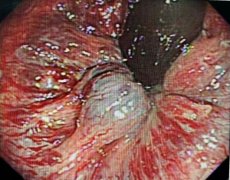

在各学科支持下,消化内科李一鸣主任,乔小伟医师在内镜下完成局部痔核聚桂醇硬化治疗,术后患者未出现便后滴血症状,疼痛消失,得到患者及家属的认可。

近年来,随着内镜技术快速发展,内镜下内痔套扎、硬化治疗技术在临床广泛开展。套扎治疗是通过内镜下的圈套装置将内痔用圈套器套扎,使痔静脉缺血、无菌坏死、痔核脱落、痔疮消失。硬化治疗医师内镜下将硬化剂注入到内痔黏膜下、基底部或痔核,产生无菌性炎症反应,黏膜下组织纤维化,血管栓塞中断痔疮的血液供应,致使痔块萎缩;松弛的黏膜可因纤维化而固定在肛管肌壁上,从而缓解脱垂症状。